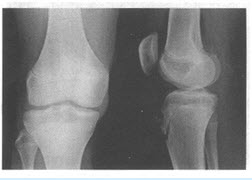

患者,男,17岁,胫骨前结节处疼痛不适1个月,局部有轻微肿胀。无发热,无明显外伤史,膝关节活动自如。

第2题,共4个问题

(单选题)患者所做检查如下图,你的诊断是()

A:胫骨结节骨软骨炎

B:胫骨化脓性骨髓炎

C:骨肉瘤

D:骨结核

E:胫骨骨折

F:软骨肉瘤

第3题,共4个问题

(多选题)请结合图像描述所见()

A:胫骨前结节见节裂

B:胫骨前结节处局部软组织肿胀

C:髌韧带增厚

D:局部有骨膜反应

E:可见有骨折线

F:死骨碎块

G:局部软组织肿块影

H:可见肿瘤骨